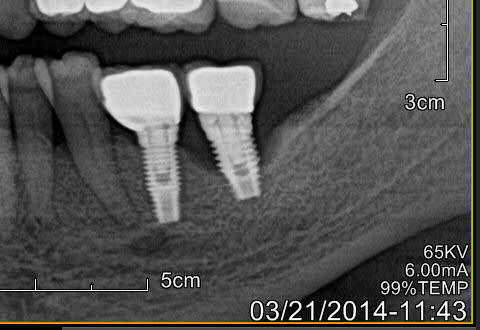

J'ai eu le cas sur une patiente avec implants sans probleme depuis 2006, debut de craterisation en 2014.

J'ai utilise le tourne a gauche d'anthogyr, et malgre le detourage a la fraise sur la profondeur la plus grande possible, j'ai bien cru que soit l'instrument soit la mandibule allaient rompre.

En fait ca ressort quand l'os autour de l'implant se rompt dans son epaisseur. L'os est reste collé sur l'implant retire.

Image1 juplas - Eugenol

Image2 nvyecp - Eugenol